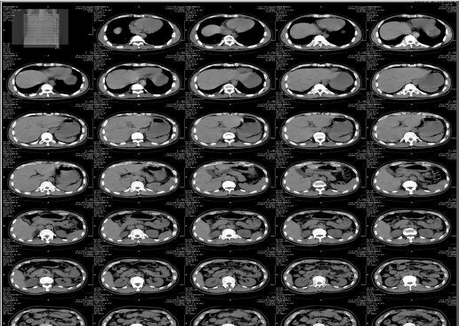

產(chǎn)品名:醫(yī)用干式膠片(噴墨 藍(lán)基 膠片)